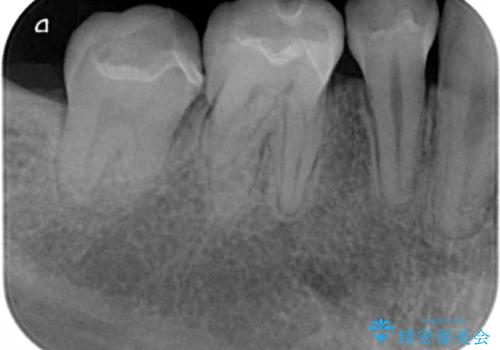

- 矯正治療が終了し、目立つ銀歯を白くやりかえたいと来院されました。

長期的な予後の期待できる銀歯を除去しセラミックインレーによるやり替えを計画します。

- 15.4万円(セラミックインレー×2)費用は治療当時の料金となります

セラミックインレーは色調を選択することができるので、歯の色に合わせ自然な色合いに仕上げることができます。